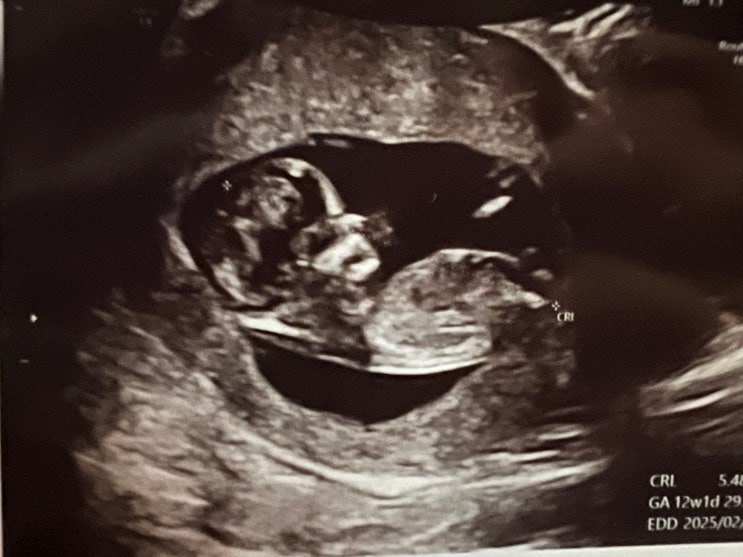

[임산부일상] 임신 확인부터 임신 24주까지의 초중기 임산부의 일상

내가 임신을 했다니... 임산부라니.. 엄마라니!! 도저히 믿기지 않는 일상을 보내고 있는 요즘. 결혼한지 3...